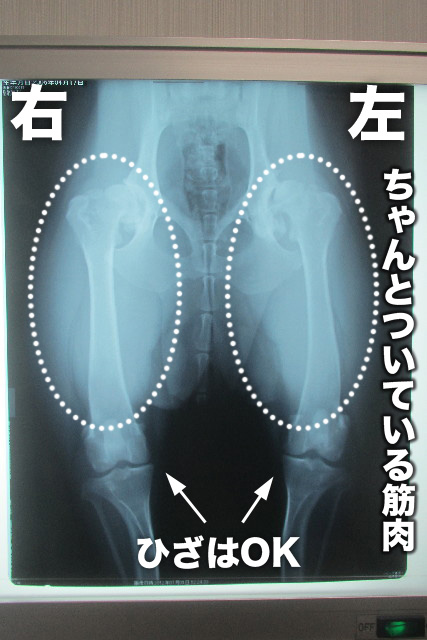

【レントゲン】

●O脚の子は膝が原因の子もいるが、もいは膝は大丈夫★('-^v)

●筋肉はちゃんとついている

→筋肉はまるでブルマをはいたみたいで可愛いかったです(笑)